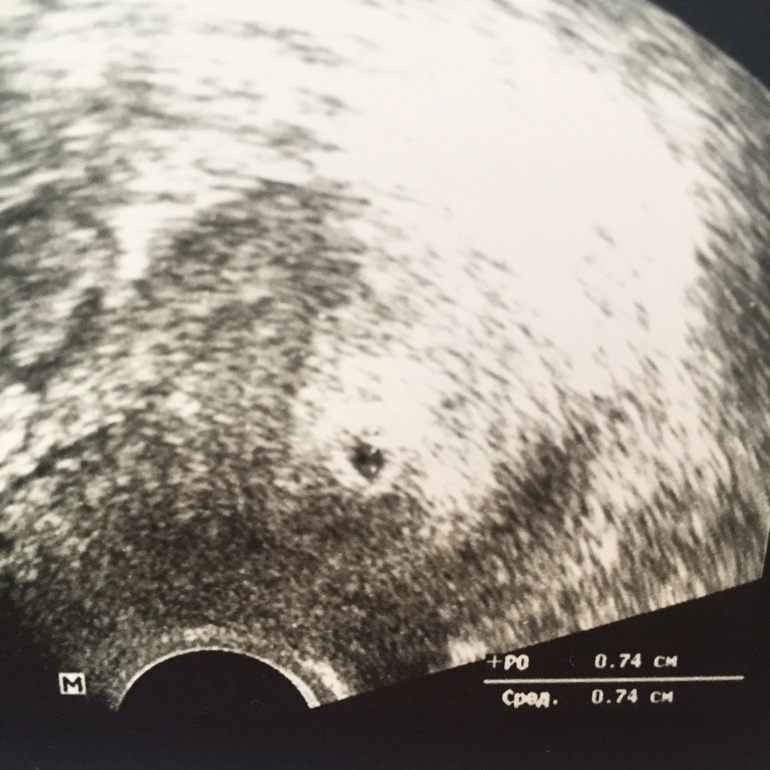

пя только 11 мм

на 6 недель тяните

растите давайте скорее, скоро и эмбриончик появится

Я вообще не понимаю как считать, по последним М, пишет 6нед и 2дня, а так 30дпп, но еще недельку гулял где-то эмбрион)

считают по размеру пя, пока оно есть. а как эмбрион появится срок считают по ктр